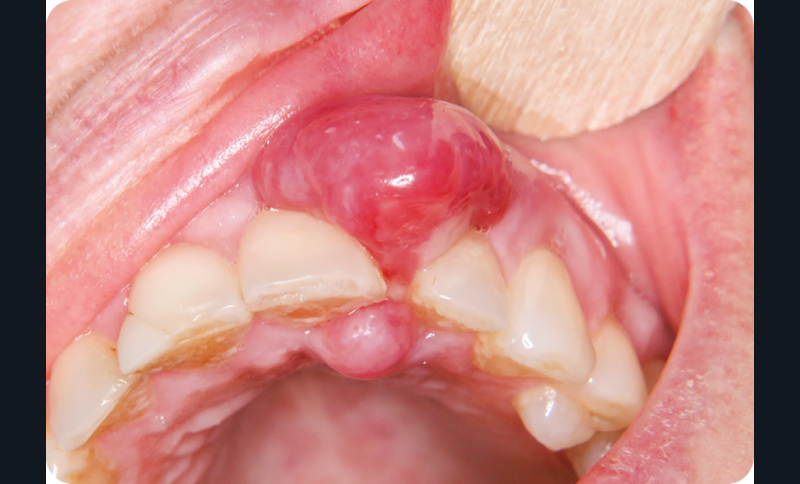

On observait un nodule gingival en bissac d’environ 1,5 cm de diamètre développé entre 21 et 22. Le nodule avait un aspect érythémateux violine et était par place ulcéré. La palpation révélait une lésion de consistance ferme. Le sondage objectivait une poche de 10 mm en vestibulaire de 22.